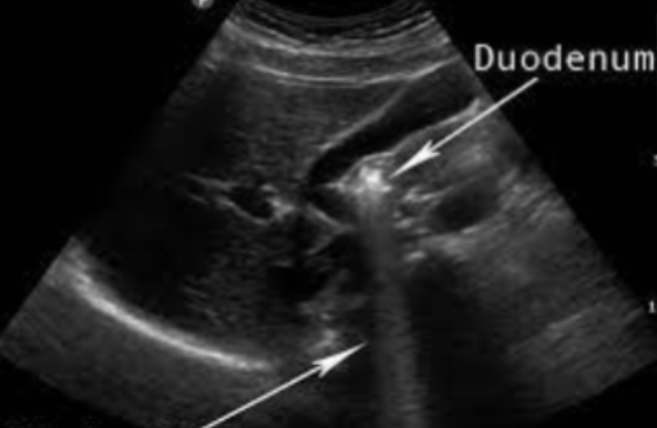

In the image, the gallbladder is located behind the bowel and is not visible. The black oval next to the bowel is this artifact mimicking the gallbladder.